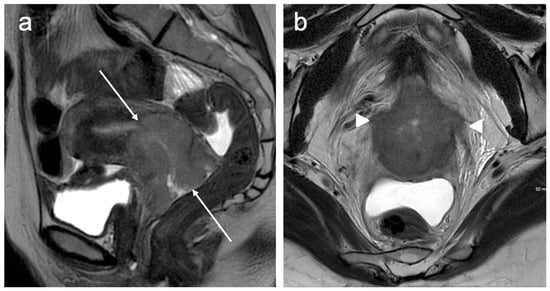

5. FIGO Stage II

6. FIGO Stage III

7. FIGO Stage IV